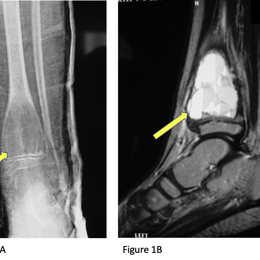

Radiographic imaging is used to help form a diagnosis of ABC. These include X-Ray, MRI, CT and Bone Scans.

An example of an ABC X-Ray (Figure 1A) and an MRI (Figure 1B) with fluid fluid levels are shown.